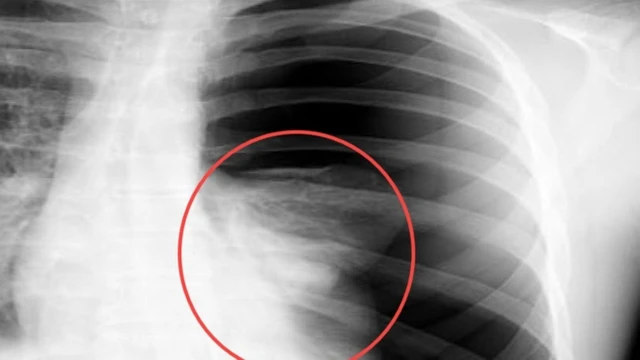

Tràn dịch màng phổi là một bệnh lý khá phức tạp và đang có xu hướng gia tăng trong công đồng. Bệnh lý này thường diễn tiến nhanh chóng và tác động trực tiếp đến sức khoẻ của người bệnh, thậm chí là dẫn đến tử vong nếu không được điều trị kịp thời. Vậy dấu hiệu tràn dịch màng phổi là gì?

Tràn máu màng phổi là một tình trạng nghiêm trọng có thể đe dọa tính mạng nếu không được điều trị kịp thời. Những người bị chấn thương ở ngực cần được kiểm tra khả năng tràn máu màng phổi để hạn chế nguy cơ diễn tiến của biến chứng trên phổi. Một số ít trường hợp cũng có thể xảy ra do những nguyên nhân khác liên quan đến những tình trạng bệnh lý tại phổi.